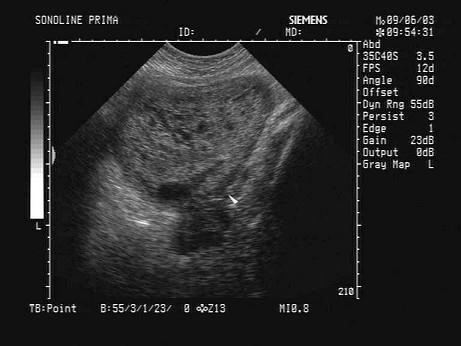

问题 女,26岁,停经3个月,HCG阳性。根据B超检查声像图如下,最可能的诊断为?(?)

选项 A.葡萄胎 B.子宫肌瘤 C.稽留流产 D.不全流产 E.绒癌

答案 A